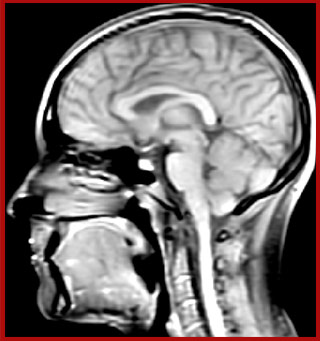

of limiting MWI to the brain, even without the cerebellum, we can now spend about the same amount of time and scan the whole brain and the cervical spinal cord, which is a huge boost for us.” Dr. Rauscher says, “For MWI we perform 3D T2 with 32 or more echoes. This used to take a long time, but with Compressed SENSE we can decrease this to ten minutes for the whole head. Because of the large field of view (FOV) on the readout direction, we even get information from the brainstem, which we previously missed when we were using the GRASE approach. Having the whole head scan is nice because it has spatial resolution, orientation and FOV that are comparable to the standard 3D clinical MS scans, including the FLAIR and 3D T2, and a 3D T1 for brain volume.”

T1 - Weighted, Myelin Water Fraction Superimposed

Spinal cord coverage

Smaller, more isotropic voxels

Excellent detail in quantitative maps

Images courtesy of Adam Dvorak, Department of Physics and Astronomy, University of British Columbia

Sagittal 3D FLAIR with 0.3 mm3 voxel volume acquired in 5:12 min. using Compressed SENSE showing a (juxta)cortical MS lesion.

QSM based on a Compressed SENSE multi-echo SWI.